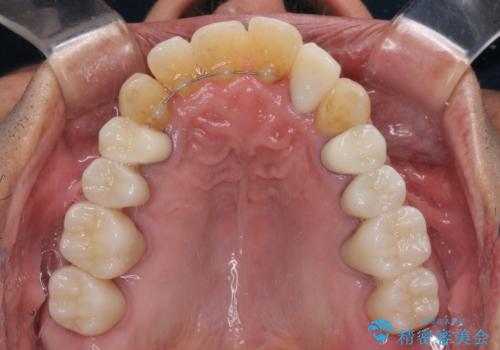

歯列不正と歯周病 総合歯科治療による全顎治療

- 前歯がのデコボコや、奥歯に咬んだときに痛みがあるとのことで来院された患者様です。

全体的に問題が多く、全てをしっかりと治療したいとのことでした。

全体的に中等度の歯周病と診断されたため、歯周外科処置やインプラントによる咬合回復から進めて行き、矯正治療による歯列改善を行った後にオールセラミッククラウンにて補綴することとしました。

歯槽骨の再生治療を行ったため、外科処置後の静置期間がながくなり、4年弱の治療期間となりました。

初診来院時には矯正治療を行うことは想像していなかったようで、治療後には咬みやすさだけでなく、前歯が大変審美的に仕上がり、患者様には大変満足していただきました。